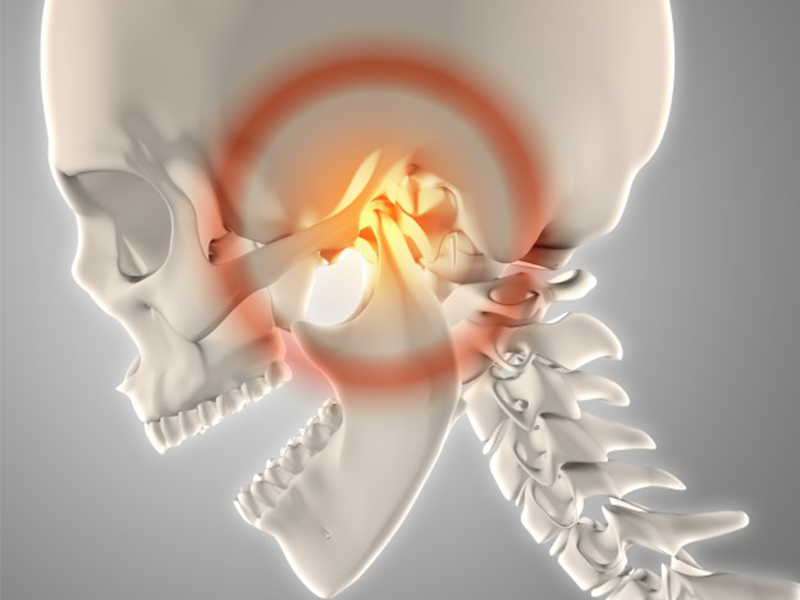

顎関節症治療について

学校歯科健診にも取り入れられている顎関節症は、むし歯・歯周病と並ぶ第三の歯科疾患ともいわれています。あごが痛む、お口が開かないなどの症状が現れるため、かたい食べ物が噛めない、あごが疲れるなどの症状が現れます。

顎関節症の治療方法

顎関節症の治療では歯を削ったり、手術をしない「保存的療法」を基本治療として行います。患者さまの日常生活が少しでも快適になるように、一緒に原因を考え、アドバイスや治療方法をご提案します。

- 薬物療法(筋弛緩薬や鎮痛剤などの投与)

- 理学療法(筋訓練やマッサージ)

- 行動療法(歯ぎしりや噛みしめ、あるいは姿勢の改善などの生活指導)

- スプリント療法(マウスピースのような装置の装着)